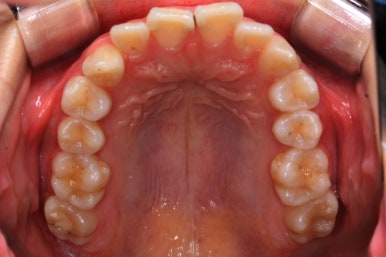

위 사진은 연산동교정치과 처음 내원하셨을 때의 입안 모습입니다. 몇 가지 모습이 관찰됩니다.

치아가 삐뚤삐뚤합니다.

위~아래 앞니가 많이 겹쳐서 아랫니가 많이 모이지 않는 "과개교합" 입니다.

앞니가 앞으로 뻐뜨러져 있습니다.